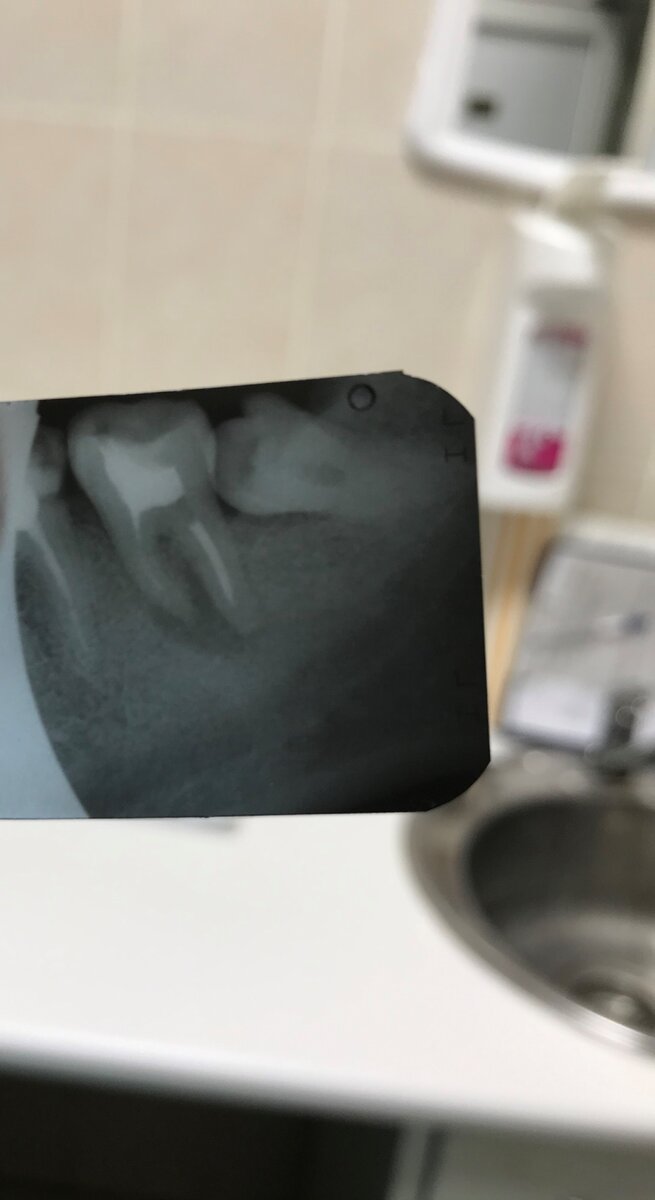

В зрелом возрасте у меня начал прорезаться зуб мудрости, причём лёжа. Все бы ничего, но это уже был 4ый зуб мудрости, и ему не хватало места. Начали болеть и кривиться передние зубы. Я долго мучилась, ждала неизвестно чего, но, в итоге решила идти и вырвать этот несчастный зуб. Пошла в нашу бесплатную поликлинику, перед удавлением меня врач отправил на рентген, который показал в соседней 7ке кисту. Врач категорически отказался вырывать 8ку, пока не вылечена киста на 7ке - или готов удалить сразу 2 зуба за 5 тысяч. В бесплатной поликлинике кисту лечить отказались, только удаление. Расспросив своих друзей, мне посоветовали врача, который занимается частной практикой. Приехала к нему на консультацию. Договорились, что он вырвет зуб за 5 тысяч, а за 10 тысяч в 2-3 приезда вылечит кисту. Причём я переспросила: 10 тысяч -это цена за 1 приём или за 2-3 -все лечение кисты? Ответ был, что цена за несколько визитов то есть за всё лечение. Единственное, он не даёт гарантии, что киста вылечится, на этот случай у него можно сразу же удалить и вкрутить шуруп для импланта. Я решила попробовать спасти зуб -как -никак свой зуб лучше импланта, да и намного дешевле.

Мои зубки